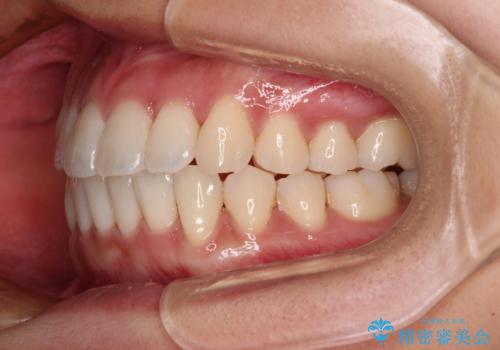

捻れた前歯をできるだけ短期間で 表側のワイヤー矯正

日々前歯の捻れが解消されていくので、歯の動きを楽しみながら矯正治療を進めることができました。